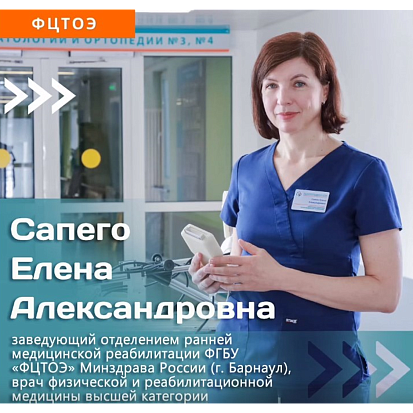

Отделение ранней медицинской реабилитации